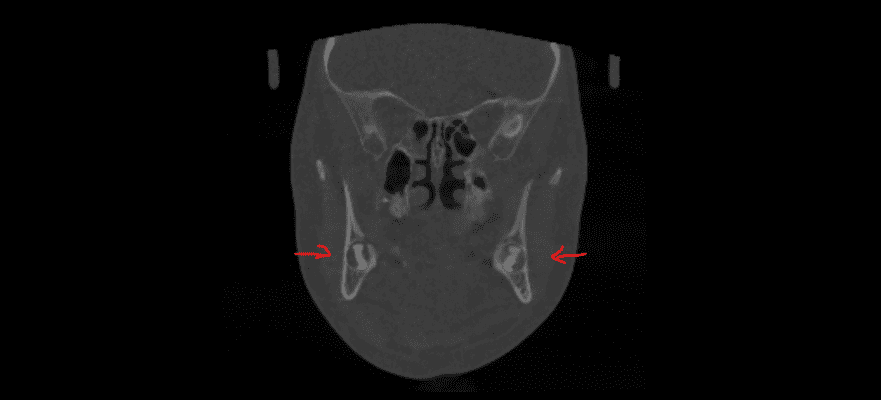

Видалення надкомплектних зубів. Бродик Богдан.

Надкомплектні зуби — це той випадок, коли зубів у зубному ряду є більше, ніж задумано. У такому випадку вони заважають повноцінному прорізуванню основних зубів та створюють ортодонтичні проблеми. Вихід у даному випадку — видалення надкомплектних зубів з подальшим ортодонтичним лікуванням. Завдяки злагодженій роботі з анестезіологічною командою проведене делікатне видалення надкомплектного зуба, ушивання рани, і тепер юна пацієнтка готова до того, аби її посмішка формувалась належним чином.

Видалення зубів мудрості. Бродик Богдан.

Видалення зубів мудрості — досить складна процедура, яка потребує високої кваліфікації хірурга. Особливо це стосується ситуації, коли видалення проводиться в ранньому віці. У даному випадку дівчинці 11 років було проведено видалення двох зубів мудрості. Перевага такої тактики полягає в тому, що зуби мудрості видаляються до того, як вони починають негативно впливати на прикус. Це дає дуже багато переваг для формування зубо-щелепної системи, але потребує майстерності лікаря.

Видалення зубів мудрості. Бродик Богдан.

Часто чуємо питання: чи можливо за один візит видалити всі зуби мудрості одномоментно. Так, це можливо, і є ситуації, коли це більш раціонально, ніж розділяти такі маніпуляції на чотири окремі візити. Але в такому випадку це потрібно робити в умовах анестезіологічного забезпечення. У даному клінічному випадку, завдяки ефективній взаємодії з анестезіологічною командою, було проведено одномоментне видалення чотирьох зубів мудрості. Тепер пацієнтка скерована до ортодонта і готова розпочинати ортодонтичне лікування.